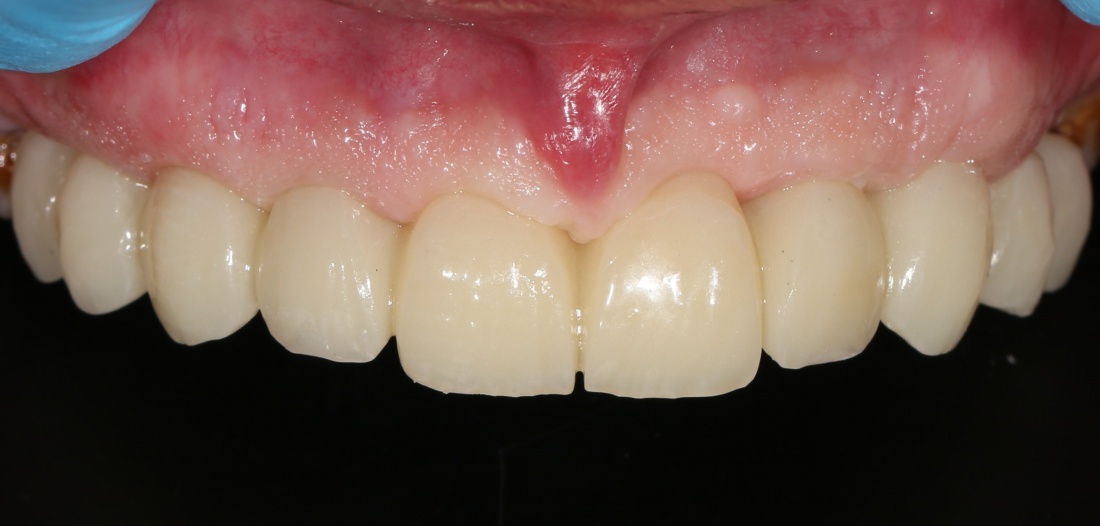

Почему всё это должен знать имплантолог? Дело в том, что суммарная длина конструкции «имплантат-абатмент-коронка» должна оставаться неизменной, если мы хотим, чтобы коронка была в прикусе и нормально функционировала. Это значит, что небольшая длина импланта должна быть компенсирована раздутым эго и большим джипом увеличением размеров супраструктуры, а именно — абатмента и коронки:

Но это еще не самое веселое. Допустим, мы решили проблему соединения «имплант-абатмент», у нас нет проблем с люфтами, а сам имплантат настолько хорошо интегрировался, что способен любую нагрузку в любом направлении. Возникает другая проблема — размер супраструктуры и соответствие ее нормальной биологической длине коронки зуба:

На фотографии выше, коронки опираются на обычные импланты, но даже в этом случае увеличение высоты супраструктуры усложняет гигиену и требует более пристального дальнейшего наблюдения. С ультракороткими имплантами, если честно, всё еще хуже.

Как будет выглядеть такая конструкция? Какой длины будут коронки? Возможно, на эстетику даже можно забить, ведь для некоторых людей красота зубов в боковом сегменте челюсти за пределами эстетически значимой зоны не так важна, но… как быть с уходом за протетической конструкцией и ежедневной гигиеной? Ведь, чем больше по размеру протез, тем сложнее за ним ухаживать. Тем больше мест, где может остаться зубной налет, а это, как вы понимаете, может привести к очень неприятным последствиям — периимплантиту, что для ультракоротких имплантов очень критично. А застревание пищи между протезом и десной? Можно ли назвать это «повышением качества жизни пациента»? Вряд ли.

В общем, уважаемые друзья, с точки зрения хорошего ортопеда, ультракороткие импланты — та еще задница. Да, для имплантолога работы меньше, поставить их очень просто, но вот когда доходит дело до протезирования, начинаются пляски с бубнами. А я. опять же, напомню, что мы должны выбирать такой план имплантологического лечения, чтобы максимально облегчить работу врачу-ортопеду. Чтобы он каждый раз, после приёма очередного пациента, делал так: